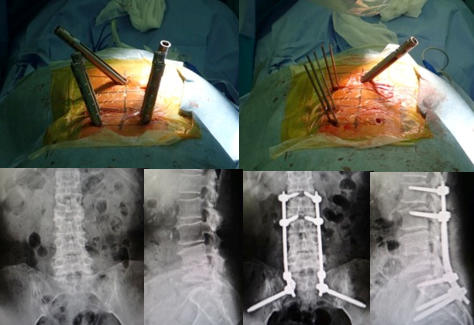

第4腰椎に著明なすべりを認め、重度の狭窄を認めます。 -

側方経路腰椎椎体間固定術(LLIF) 椎間板に大きなスペーサーが挿入され、また経皮的に椎弓根スクリューの挿入とロッドの連結がなされ、第4腰椎のすべりが矯正され固定されています。